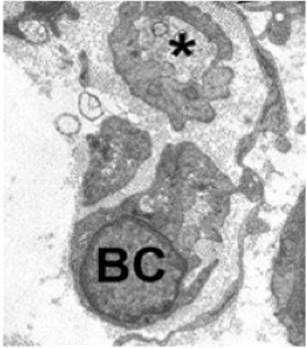

Este proceso local axonal consiste en la dediferenciación de células de Schwann maduras en células especializadas de reparación o de Büngner (figura 4). Esto último se ha considerado un estado de activación y un nuevo grado de plasticidad celular que representa un nuevo tipo de células especializadas para la regeneración de los nervios periféricos, al crear vías que guían el axón a su objetivo [4], por medio de pistas de regeneración denominadas bandas de Büngner (figura 5), que llevan las fibras nerviosas hacia el destino apropiado y la restauración de la función. Además, favorecen la supervivencia de las neuronas periféricas afectadas y logran la preservación de axones que, de otra forma, morirían, así como la apertura de la barrera hematoneural, con el fin de reclutar macrófagos en el sitio de lesión para el desbridamiento de mielina.